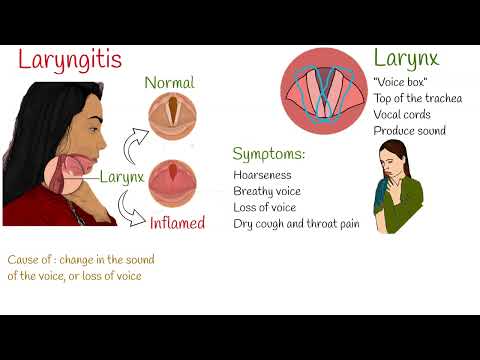

Laryngitis treatment (plus 4 home remedies)

What is laryngitis? How to treat laryngitis?

Laryngitis symptoms can usually be managed at home without antibiotics. However, you should see a doctor if you have been experiencing symptoms for two weeks or more.

To alleviate laryngitis symptoms and to speed up recovery, there are various home remedies and ways you can treat laryngitis naturally: